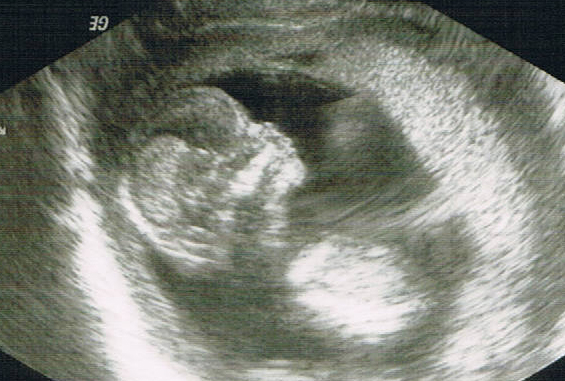

Ultraschallbild (Velen)

Ultraschall – jedes Mal schlägt mein Herz höher. Plötzlich kriege ich eine Gänsehaut. Es scheint so, als würde mein Baby mir zuwinken. Dann betrachten wir das Seitenprofil. Wow – das Köpfchen ist ja gut zu erkennen.